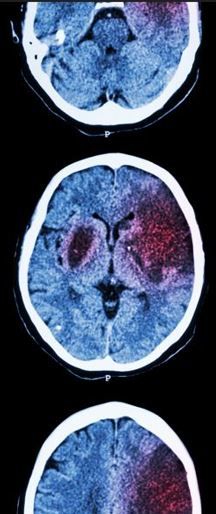

Investigators recruited ARCADIA participants from 185 sites in the National Institutes of Health StrokeNet network and the Canadian Stroke Consortium. Inclusion criteria required age greater than 45 years, a clinical diagnosis of cryptogenic stroke, brain imaging to rule out hemorrhagic stroke and brain MRI and CT to rule out other etiologies. Key exclusion criteria, among other factors, included any history of AF or left ejection fraction less than 30%.1